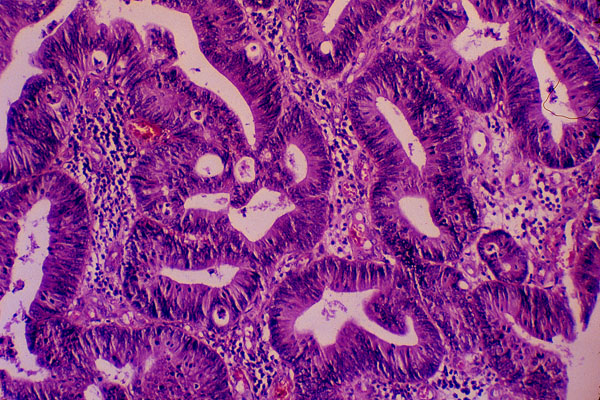

Adenocarcinoma of the colon, histology

The multilayered epithelium lining the glandular lumina is composed of hyperchromatic cells.